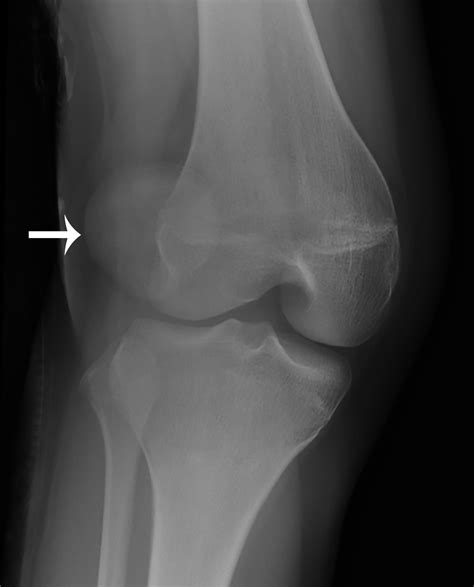

• Imaging Tests: X-rays, MRI, or CT scans to visualize the patella and surrounding structures. These tests can help identify any anatomical abnormalities or soft tissue injuries.